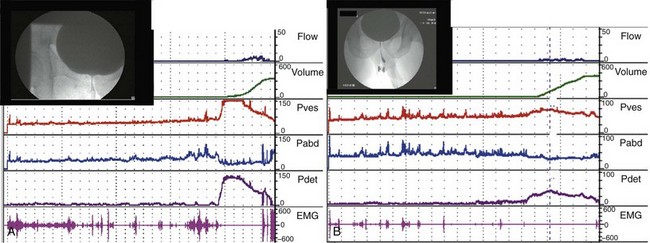

The second type of leak point pressure is the detrusor leak point pressure (DLPP), which is a measure of detrusor pressure in patients with decreased bladder compliance. It is defined as the lowest detrusor pressure at which urine leakage occurs in the absence of either a detrusor contraction or increased abdominal pressure (Abrams et al, 2002) (see Fig. 62–5). The higher the urethral resistance, the higher the DLPP. One can imagine that in a poorly compliant bladder, if outlet resistance is low, incontinence will occur at a relatively low or “safe” pressure. However, if outlet resistance is high, the pressure in the bladder will continue to increase as the bladder fills. There is potentially less incontinence, but eventually the pressure is transmitted to the upper tracts (Fig. 62–8).

Figure 62–8 Outlet resistance causes impaired compliance. Urodynamic (UDS) studies of two children with the same neurologic problem and symptoms but dramatically different findings. A, UDS tracing of a young boy with spina bifida who is incontinent in between catheterizations. The study shows a low-pressure system with poor outlet resistance and stress incontinence (ALPP demonstrated) and a low DLPP. His upper tracts are protected. B, UDS tracing of a young girl with spina bifida who is incontinent in between catheterizations. The study shows a high-pressure system with strong outlet resistance and a high DLPP. There was no stress incontinence. Her upper tracts are at risk. The difference in these two cases is difference in storage pressures caused by the difference in outlet resistance.

From a clinical perspective, DLPP is most useful in patients with lower motor neuron disease causing “decentralization” and in non-neurogenic patients with low bladder compliance (after multiple bladder surgeries, radiation, and tuberculous cystitis). The higher the DLPP, the more likely is upper tract damage because intravesical pressure is transferred to the kidneys. McGuire (1981) documented the deleterious effects that a detrusor high-leak point pressure has on the upper urinary tracts; detrusor leak point pressures greater than 40 cm H2O result in hydronephrosis or vesicoureteral reflux in 85% of myelodysplastic patients.

The significance of an elevated DLPP is that bladder pressures are getting too high before the “pop-off” mechanism of urethral leakage occurs. In most cases treatment is aimed at lowering bladder pressures, so the DLPP is never reached. In some cases DLPP can be lowered by decreasing outlet resistance, for example, with a sphincterotomy in a patient with DESD.